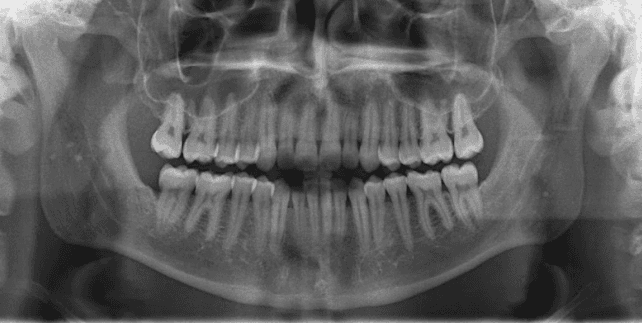

Diagnosis: Class III malocclusion, edge-to-edge anterior relationship, lower anterior crowding

X-RAYS